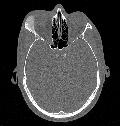

Fibröse Dysplasie

.:. Bilder

Home Pfeil Regensburg_Vor_OP